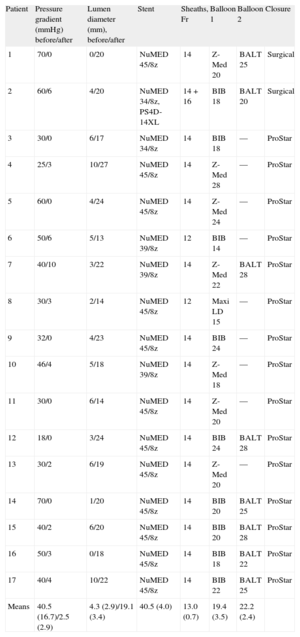

Eleven patients had native coarctation and 6 patients had recoarctation, which was secondary to end-to-end anastomosis in 5 patients and patch enlargement in 1 patient. The CS was electively implanted in 16 patients, whereas 1 patient underwent emergency implantation due to aortic rupture after expansion of a conventional stent11 (patient 2, Tables 1 and 2). The CS used was 40 (4) mm long, mounted on 19 (3) mm-diameter balloons, which correlated well with aortic diameter (18 [4] mm) before the coarctation point. In 8 patients, the distal portion was redilated with a larger balloon (25 [3] mm diameter). Stents were implanted directly except when there was total occlusion or very severe stenosis, in which case, in addition to the special technique described, the vessel was previously dilated using 8-10mm diameter balloons (patient 1 and patient 16, Tables 1 and 2).

Procedural Characteristics

| Patient | Pressure gradient (mmHg) before/after | Lumen diameter (mm), before/after | Stent | Sheaths, Fr | Balloon 1 | Balloon 2 | Closure |

| 1 | 70/0 | 0/20 | NuMED 45/8z | 14 | Z-Med 20 | BALT 25 | Surgical |

| 2 | 60/6 | 4/20 | NuMED 34/8z, PS4D-14XL | 14+16 | BIB 18 | BALT 20 | Surgical |

| 3 | 30/0 | 6/17 | NuMED 34/8z | 14 | BIB 18 | — | ProStar |

| 4 | 25/3 | 10/27 | NuMED 45/8z | 14 | Z-Med 28 | — | ProStar |

| 5 | 60/0 | 4/24 | NuMED 45/8z | 14 | Z-Med 24 | — | ProStar |

| 6 | 50/6 | 5/13 | NuMED 39/8z | 12 | BIB 14 | — | ProStar |

| 7 | 40/10 | 3/22 | NuMED 39/8z | 14 | Z-Med 22 | BALT 28 | ProStar |

| 8 | 30/3 | 2/14 | NuMED 45/8z | 12 | Maxi LD 15 | — | ProStar |

| 9 | 32/0 | 4/23 | NuMED 45/8z | 14 | BIB 24 | — | ProStar |

| 10 | 46/4 | 5/18 | NuMED 39/8z | 14 | Z-Med 18 | — | ProStar |

| 11 | 30/0 | 6/14 | NuMED 45/8z | 14 | Z-Med 20 | — | ProStar |

| 12 | 18/0 | 3/24 | NuMED 45/8z | 14 | BIB 24 | BALT 28 | ProStar |

| 13 | 30/2 | 6/19 | NuMED 45/8z | 14 | Z-Med 20 | — | ProStar |

| 14 | 70/0 | 1/20 | NuMED 45/8z | 14 | BIB 20 | BALT 25 | ProStar |

| 15 | 40/2 | 6/20 | NuMED 45/8z | 14 | BIB 20 | BALT 28 | ProStar |

| 16 | 50/3 | 0/18 | NuMED 45/8z | 14 | BIB 18 | BALT 22 | ProStar |

| 17 | 40/4 | 10/22 | NuMED 45/8z | 14 | BIB 22 | BALT 25 | ProStar |

| Means | 40.5 (16.7)/2.5 (2.9) | 4.3 (2.9)/19.1 (3.4) | 40.5 (4.0) | 13.0 (0.7) | 19.4 (3.5) | 22.2 (2.4) |

After the procedure, we observed a decrease in pressure gradient from 40 (16) mm to 2 (2) mmHg (P<.001) and an increase in lumen diameter from 4 (2) mm to 19 (3) mm (P<.001). Finally, aortography was performed and the femoral artery closed, surgically or by using the ProStar XL system. No local complications occurred, except in patient 12, who had a hematoma that resolved spontaneously. No patient had any complication at the iliac-femoral level that required stenting.